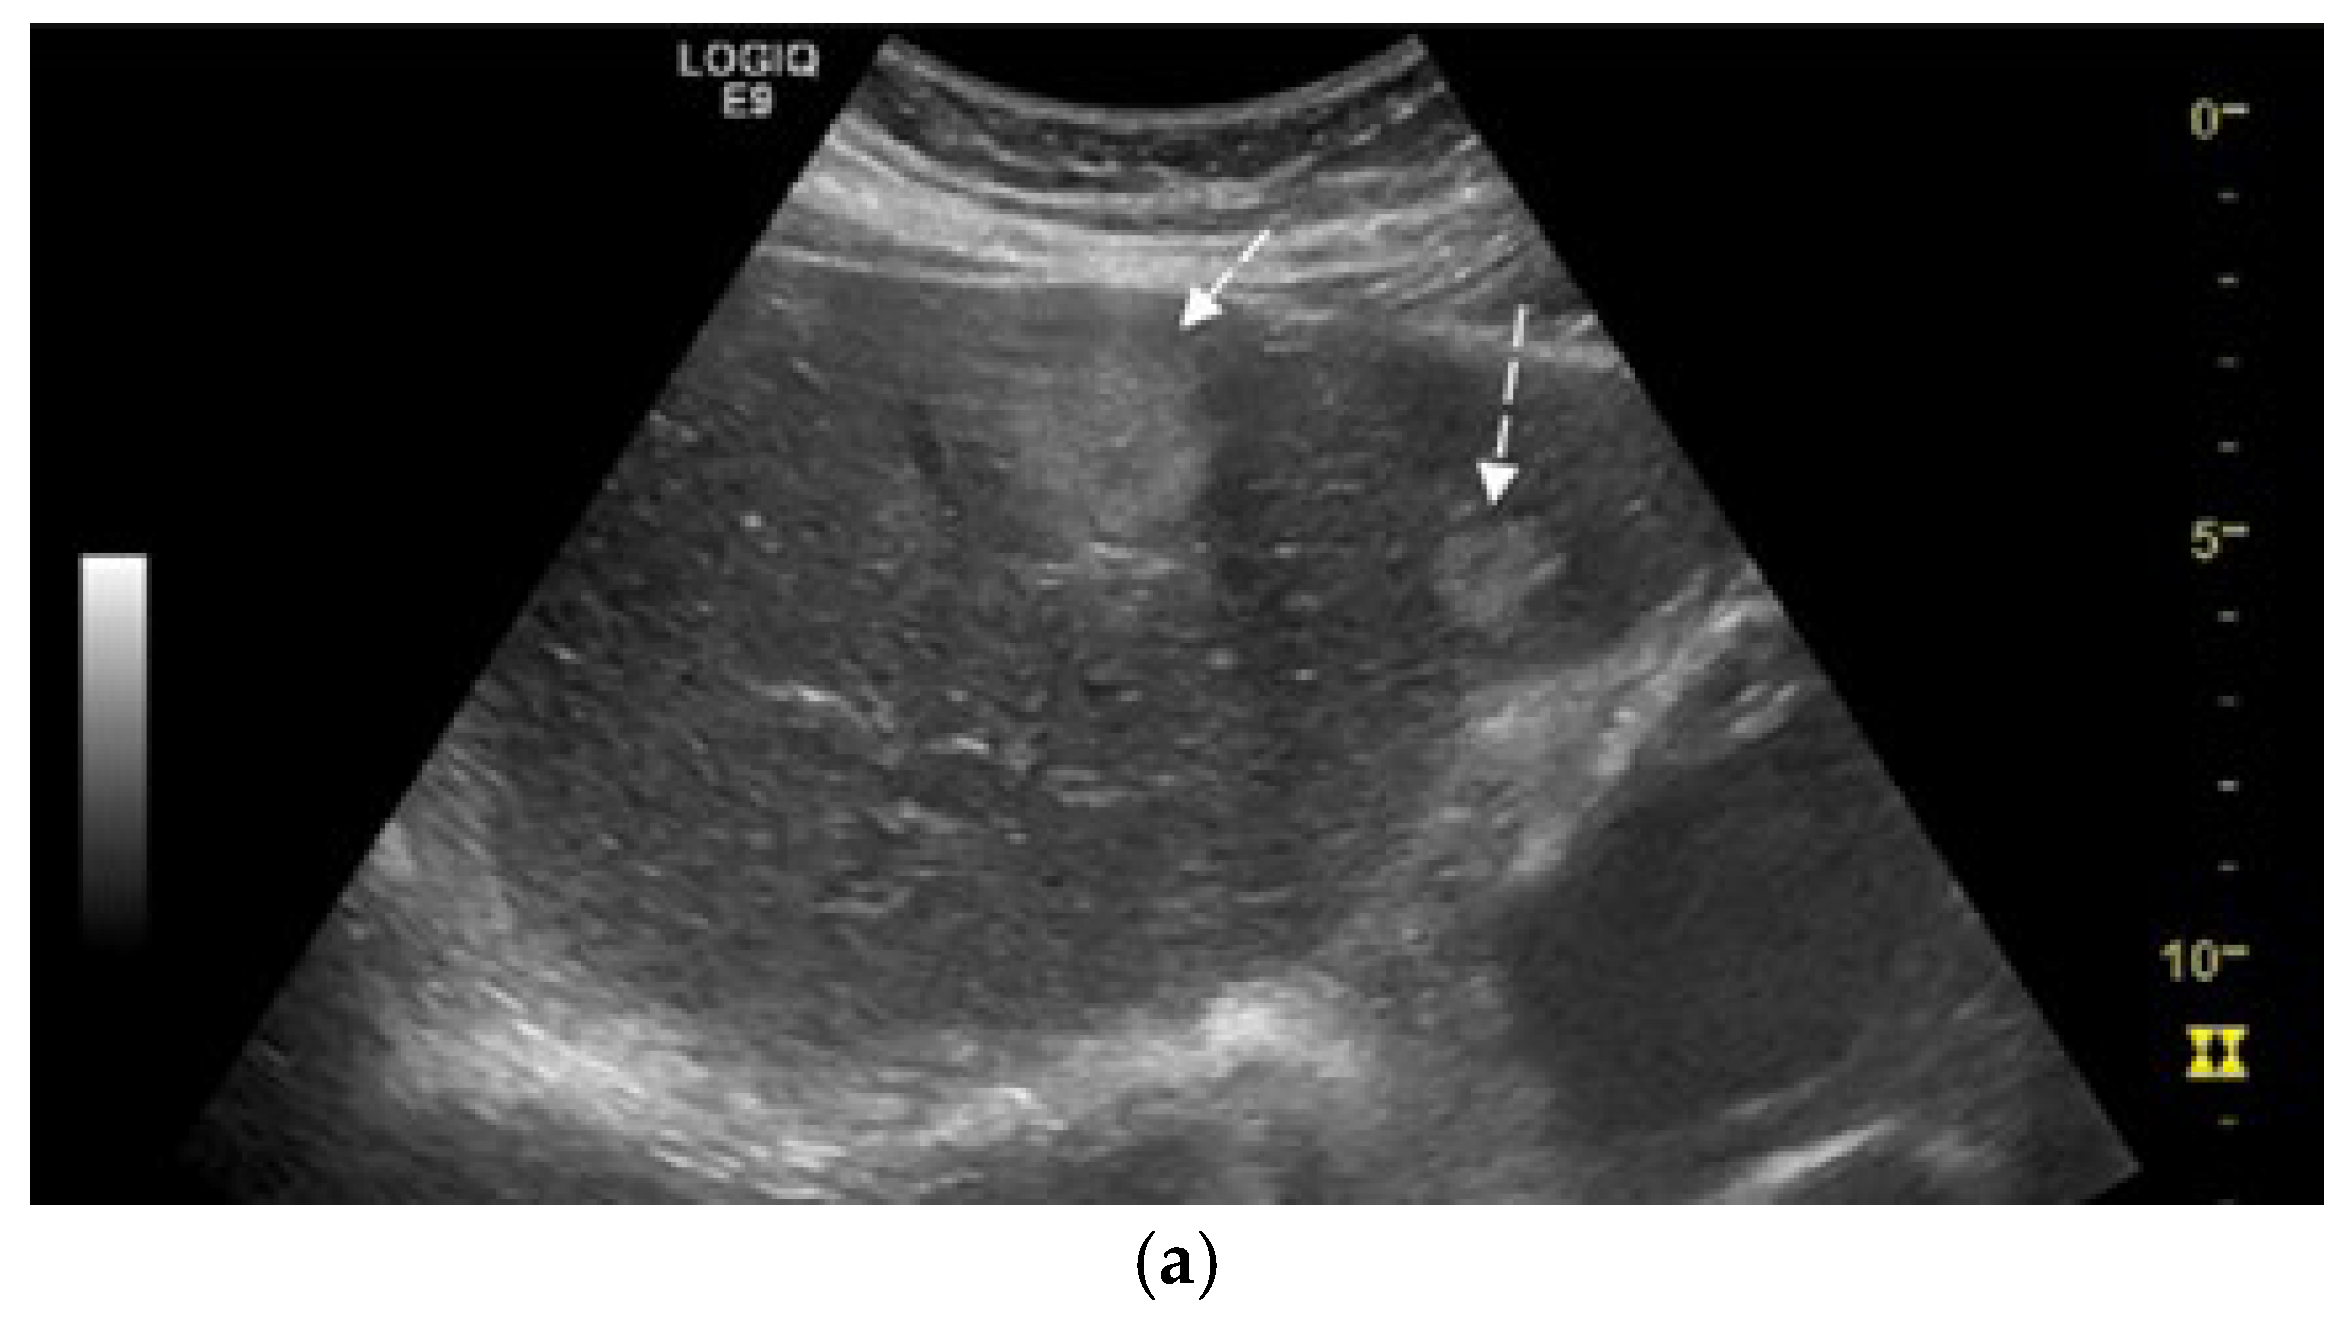

We report the case of a 67-year-old man, presented with intermittent tiredness for about three months, without associated weight loss, fever, or jaundice. The symptom was mild and episodic, occurring several times per week, and not linked to exertion or other systemic complaints. He denied abdominal pain, gastrointestinal bleeding, changes in bowel habits, cough, or flushing. From past medical history we mention chronic hepatitis C virus infection, diagnosed eight years earlier (with liver stiffness 12 kPa on transient elastography). He achieved sustained virologic response (SVR) after treatment with direct-acting antivirals (Sofosbuvir–Ledipasvir). His history also included gastric resection with gastroduodenal anastomosis for peptic ulcer disease 23 years ago, and endoscopic resection of a sessile polyp in the descending colon four years ago, confirmed as a low-grade adenomatous polyp. At the time of presentation, the patient was alert and hemodynamically stable, with vital signs within normal ranges. Physical examination revealed no jaundice, no hepatosplenomegaly, no ascites, or palpable abdominal mass, and cardiopulmonary and neurologic examinations showed no abnormalities. Laboratory investigations were within normal limits, including normal hepatic and renal function. Tumor marker levels—alpha-fetoprotein (AFP), carbohydrate antigen 19-9 (CA 19-9), and carcinoembryonic antigen (CEA)—were also within normal ranges. Abdominal ultrasound revealed three hyperechoic hepatic nodules: the largest, measuring 30 mm, in segment IVa (Figure 1a), with additional lesions in segment III (left lobe) and segment VIII (right lobe). Contrast-enhanced ultrasonography (CEUS) was performed using sulfur hexafluoride microbubbles (SonoVue®), administered as an intravenous bolus of 2.4 mL followed by a 5 mL saline flush. Arterial-phase enhancement of the hepatic nodules was observed at 10 s, with very early washout occurring at 29 s post-injection. This pattern is suggestive of malignant formations, most likely liver metastases (Figure 1b).

Figure 1.

(a) Abdominal ultrasound B-mode image capturing two hyperechoic nodules in left liver lobe (segment IVa and III) with heterogeneous, irregular contours (white arrows). (b) Abdominal ultrasound in CEUS mode at the end of the arterial phase demonstrates earlier contrast washout of both nodules compared to the rest of the liver parenchyma (white arrows).

Diagnosis relies on a multimodal approach, integrating serological test, morphological imaging, functional imaging with histopathological evaluation, and immunohistochemical profiling. Available serological tests for NENs include chromogranin A (CgA), serotonin, 5-hydroxyindoleacetic acid (5-HIAA), gastrin, insulin, proinsulin, C-peptide, glucagon, vasoactive intestinal peptide (VIP), pancreatic polypeptide (PP), calcitonin, adrenocorticotropic hormone (ACTH), somatostatin, and neuron-specific enolase (NSE). [18] Conventional ultrasound often shows strong echoic nodules but lacks specificity. CEUS is more valuable, often revealing a characteristic “fast forward and fast out” arterial hyperenhancement pattern [42]. Hepatic metastases from NENs typically present as hypervascular, ring-enhancing lesions during the arterial phase [17]. However, atypical presentations, such as pseudocystic metastases due to necrosis or hemorrhage, can mimic simple cysts, complicating diagnosis [16]. CT and magnetic resonance imaging (MRI) are standard imaging modalities for the detection and characterization of both primary neuroendocrine tumors and associated liver metastases. In our case, CT scan not only confirmed the presence of hepatic lesions but also identified an additional tumor site in the mediastinum. Functional evaluations are used to detect somatostatin receptor expression on tumor surfaces. Common techniques include 68Ga-DOTATATE PET, 64Cu-DOTATATE PET, 68Ga-OTATOC PET, and PET-CT with fluorodeoxyglucose for non-functional lesions [9,18]. These imaging methods are invaluable for staging, identifying the primary tumor, and guiding treatment decisions [43]. A limitation of this case report is the absence of functional nuclear medicine imaging, such as 68-Gallium-DOTATATE PET/CT and 18F-FDG-PET/CT. While these examinations are integral to the staging and characterization of many neuroendocrine neoplasms, the decision to forego them was made deliberately by the multidisciplinary team.